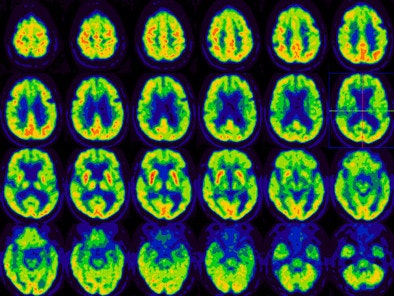

In the analysis, all patients demonstrated a certain degree of hypometabolism in the primary motor cortex as expected for ALS. "In the other regions of the cortex," Talanow added, "three patients appeared normal for their age and eight patients demonstrated regional hypometabolism in the nonmotor cortex areas."

Of the eight patients with abnormal cortical hypometabolism, two patients demonstrated a pattern of frontotemporal dementia, while one patient was consistent with Alzheimer's disease. One patient demonstrated asymmetric left frontal, parietal, temporal hypometabolism reminiscent of progressive aphasia syndrome. The remaining four patients demonstrated diffuse cortical hypometabolism.